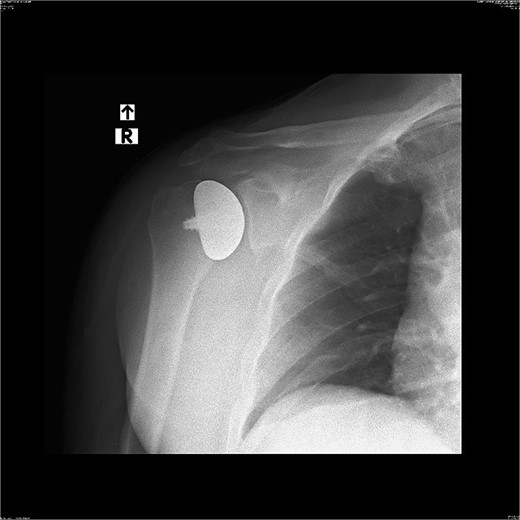

Patient is a 67-year-old male who participated in a road accident on 28 April 2020. As a result of the accident, the motorcycle driver suffered a direct injury to his right shoulder. Immediately after this event, the patient was transported, diagnosed, and treated in the Emergency Ward, where shoulder contusion was diagnosed.

X-ray images can be found in Figs 1 and 2.

After the diagnosis at EW, the decision was made to pursue with the conservative treatment.